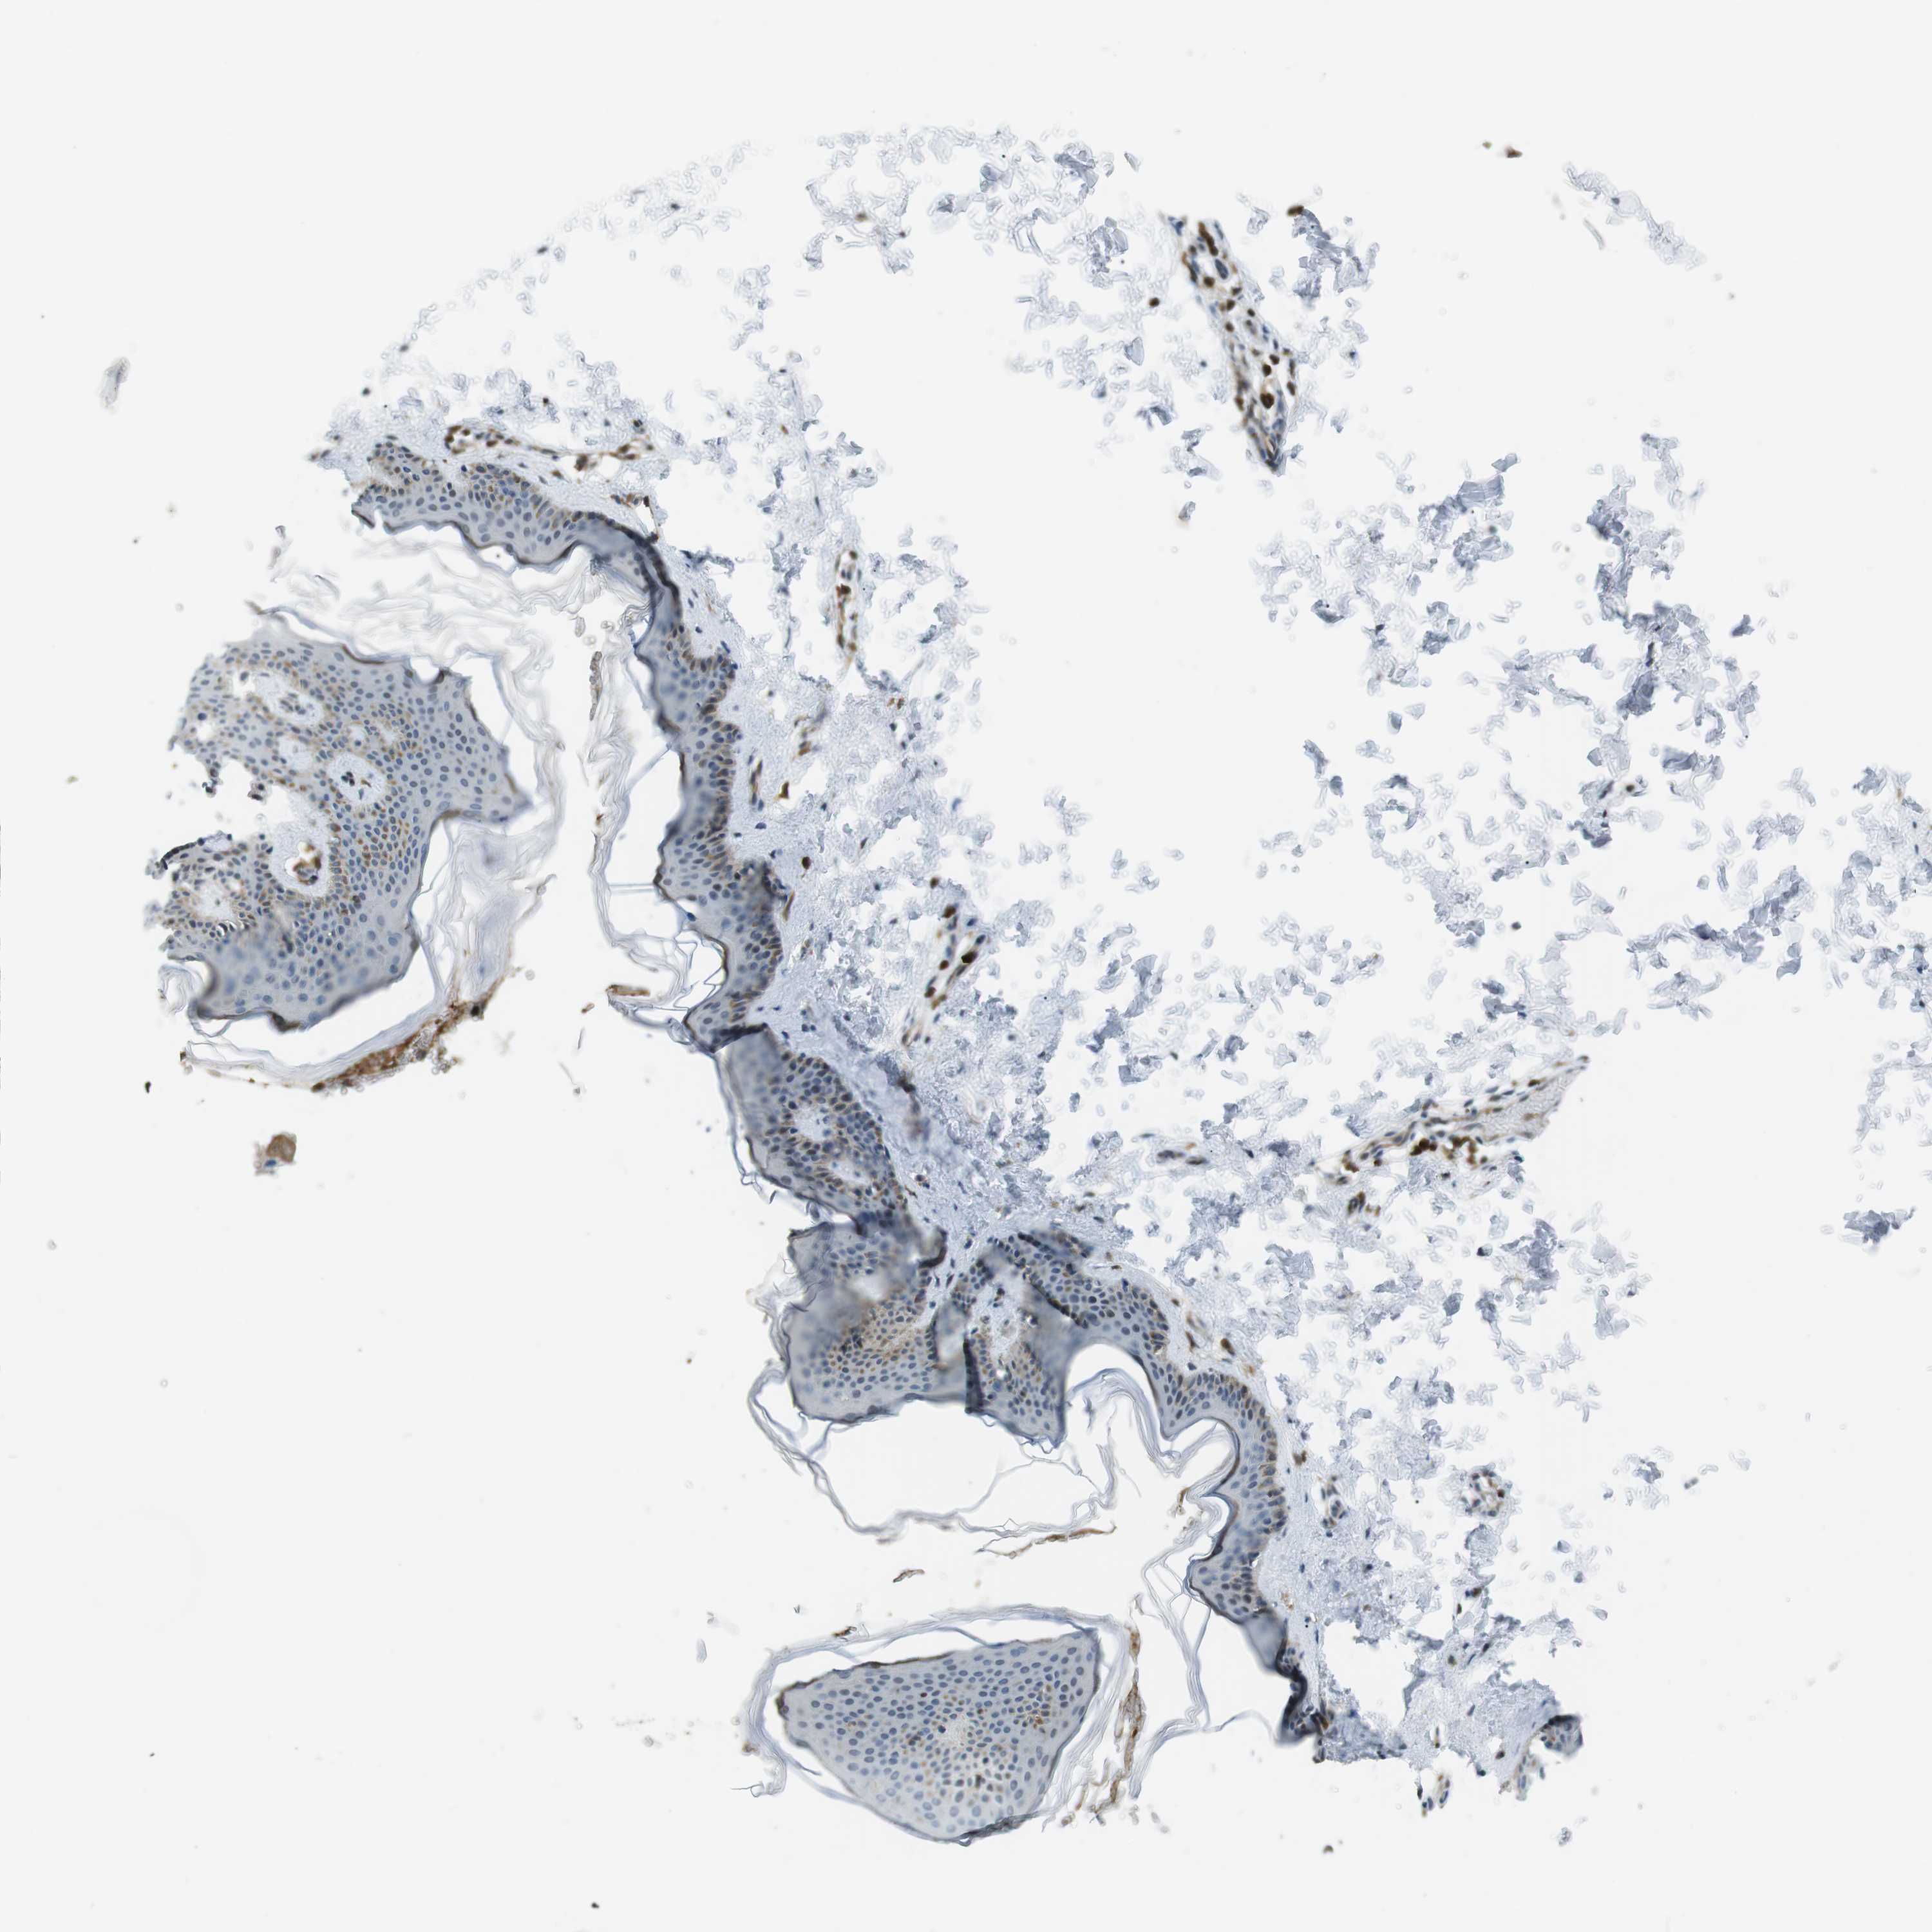

SKIN 2 - Antibody stainingi

Antibody staining in the annotated cell types in the current human tissue is reported as not detected, low, medium, or high, based on conventional immunohistochemistry profiling in selected tissues. This score is based on the combination of the staining intensity and fraction of stained cells. Each image is clickable and will lead to virtual microscopy that enables deeper exploration of all samples and also displays staining intensity scores, fraction scores and subcellular localization as well as patient and tissue information for each sample.

Antibody HPA015083

Epidermal cells Not detected